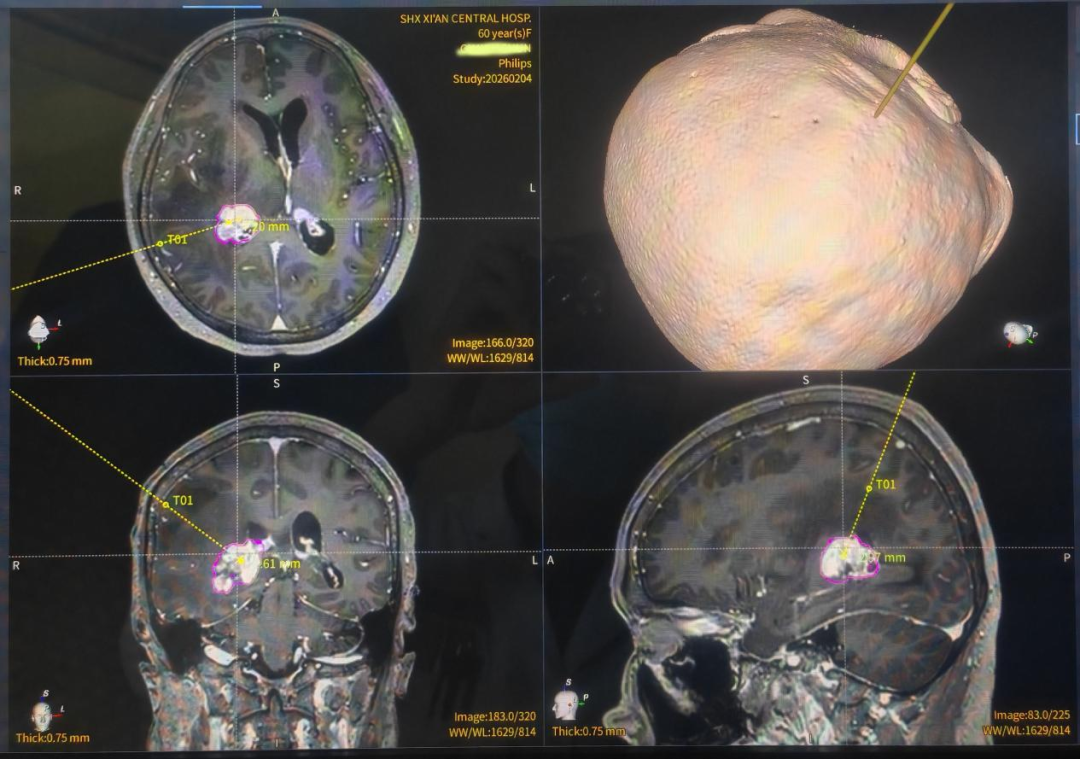

患者因头痛5日、加重2日就诊外院,影像提示颅内占位病变,为求进一步诊治经熟人介绍来到西安市中心医院找神经外科杨彦平主任医师救治。经杨主任治疗组详细检查,明确病变位于右侧丘脑及脑室三角区——位置深、毗邻重要功能结构,传统开颅手术创伤大、风险高,且术前明确病理性质是制定后续治疗方案的关键。后经龙主任组织全科医护人员进行详细讨论,大家一致认为:面对这一“位置刁钻”的病灶,神经外科团队决定采用手术机器人辅助下的精准穿刺活检方案。

手术于2026年2月10日进行。在龙乾发主任统筹指导下,带领杨彦平主任医师、罗强副主任医师及苗宇副主任医师团队,大家凭借娴熟的机器人操作技术,通过术前影像融合与智能路径规划,在三维可视化界面上精准避开血管及功能区,仅以微小创口便完成靶点定位、入路设计与实时导航。在机器人机械臂稳定、精细的辅助下,术者仅用一小时顺利获取足量、优质的病变组织,手术全程流畅高效。